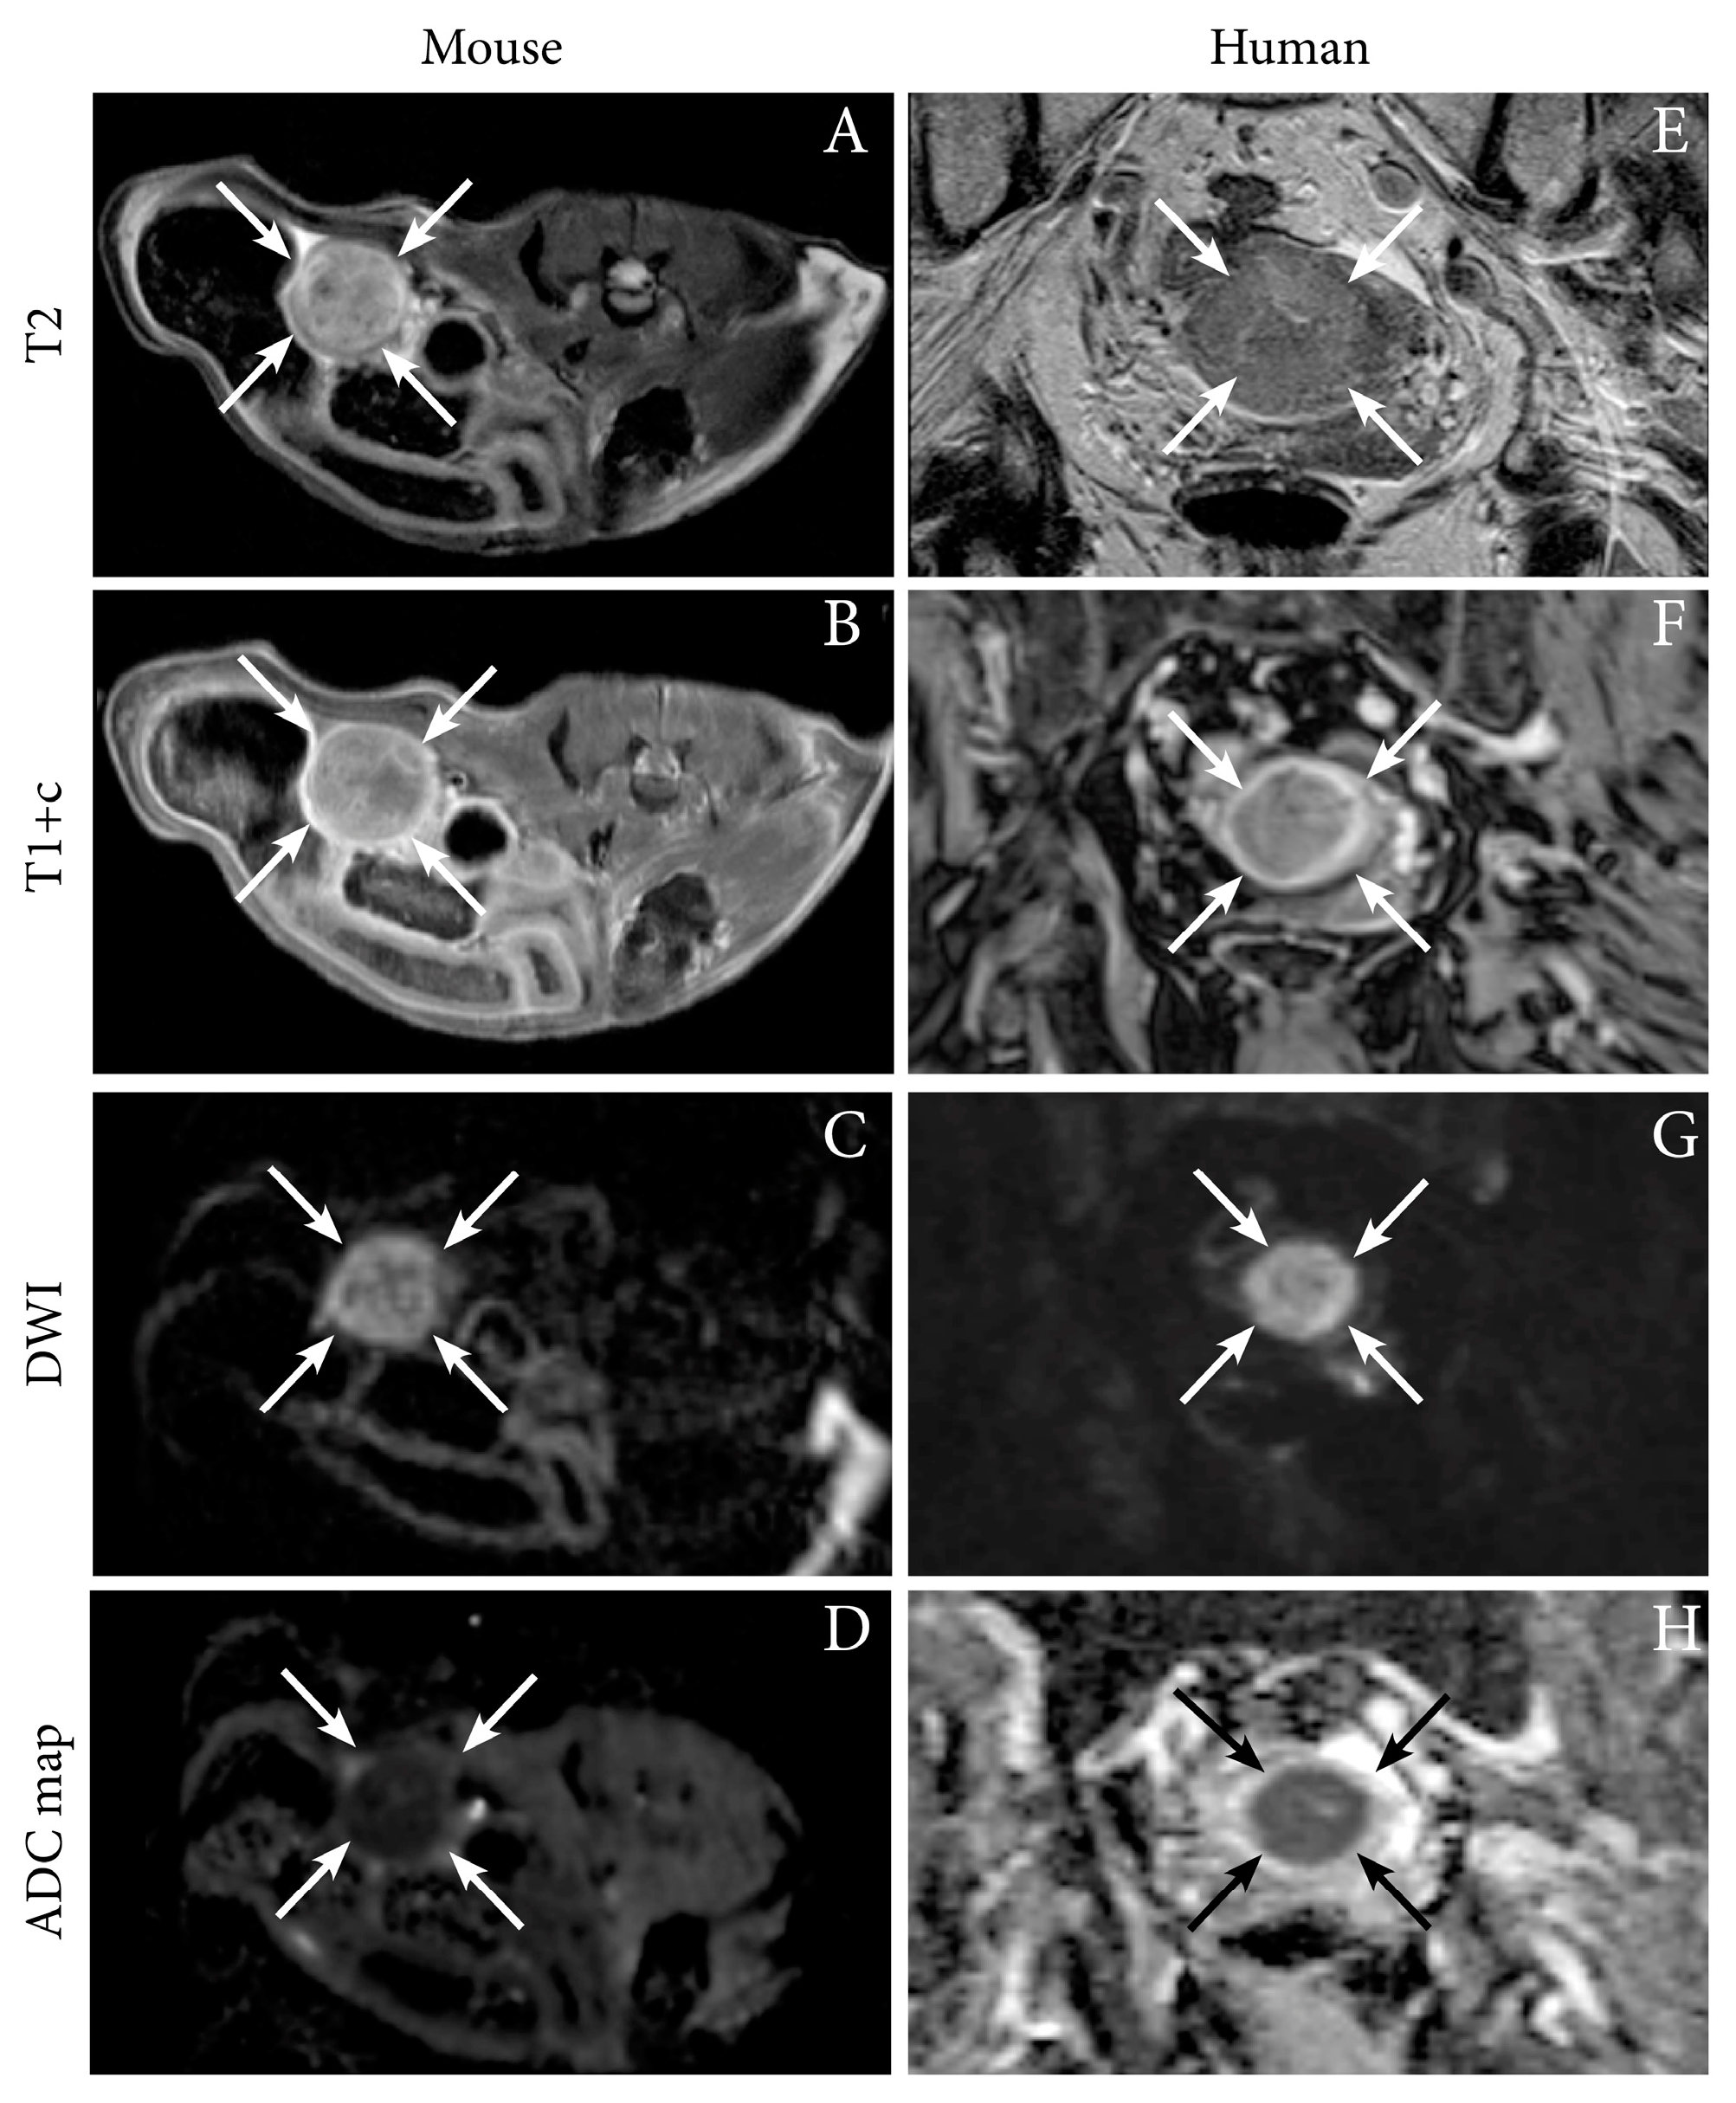

We have successfully imaged an orthotopic mouse model of EC using MRI, illustrating the feasibility of anatomical MR sequences (T1 and T2-weighted) to depict tumor growth in the uterine horns in mice [12]. Interestingly, the hyperintense tumor signal on T2-weighted series and the hypointensity of the tumor (relative to the surrounding myometrium) on contrast-enhanced (CE) T1-weighted series resemble that observed in human EC (Figure 1). Furthermore, the tumors in mice also exhibit restricted diffusion on DW-MRI with hyperintensity on high b-value images and corresponding low ADC value on the ADC map, being similar to that characteristically observed in humans (Figure 1, Table 1) [12]. For further insight into characteristic imaging findings at conventional imaging and novel promising imaging methods in human EC, we direct the readers to our recent review [16].

Figure 1.

Axial magnetic resonance (MR) images depicting tumor (arrows) in an orthotopic endometrial cancer (EC) mouse model (Ishikawa cells) (A–D), and corresponding axial MRI images visualizing a uterine tumor (arrows) in an 87-year-old woman with EC (grade 2 endometroid, FIGO stage IIIC1; same patient as in Figure 2) (E–H). (A,E) T2-weighted images depict hyperintense tumors and (B,F) T1-weighted contrast-enhanced images (T1+c) depict moderately enhancing uterine tumors. (C,G) Both the preclinical- and human tumors exhibit restricted diffusion with hyperintensity on high b-value diffusion-weighted imaging (DWI) and (D,H) corresponding hypointensity on the apparent diffusion coefficient (ADC) maps. Images A–D are reproduced under the open access CC BY license from a previous publication [12].